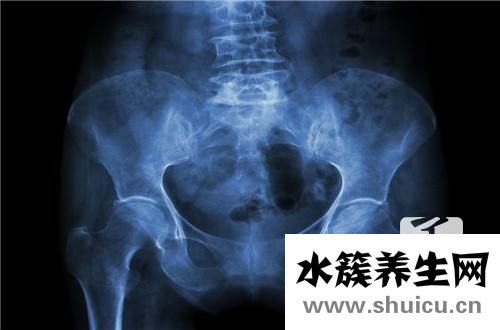

1.X線檢查

在X線x光片上由此可見挨近關節面處的髂骨皮層出現壞死性改變,骨質增生呈高密度狀,坐落于骶髂關節下1/2處,且多呈三角形;骶髂關節空隙齊整、清楚,關節面及骨質增生無毀壞征。以一側多見,亦有雙側者。